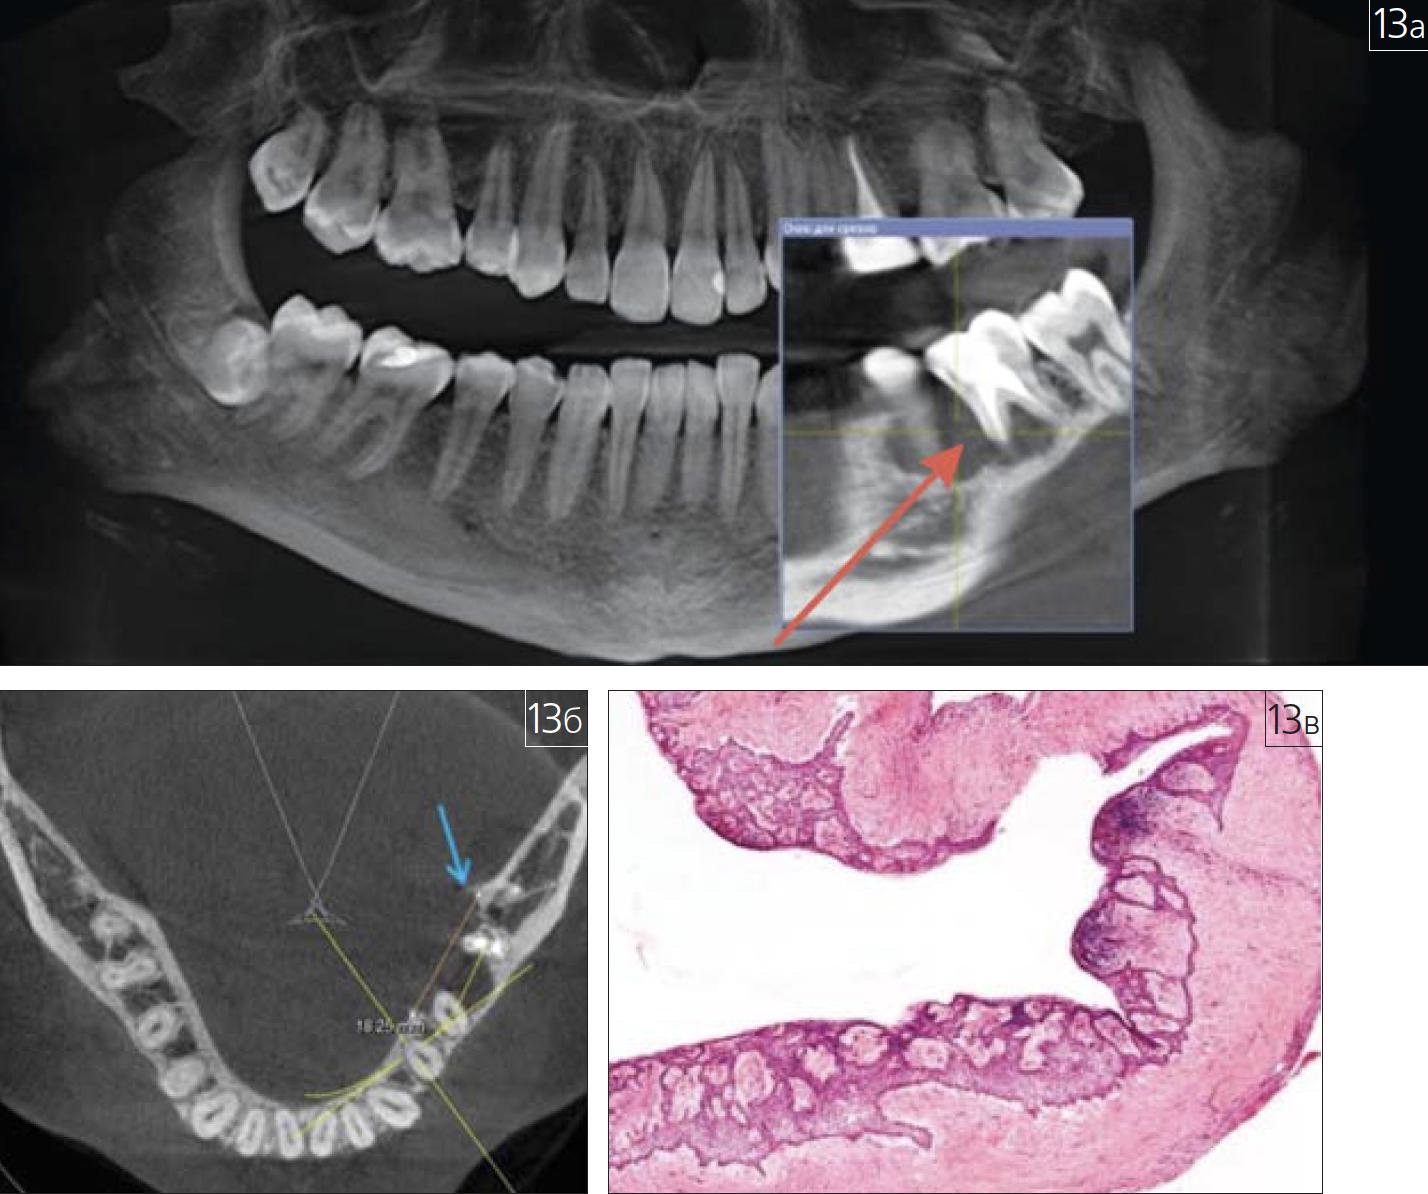

Особое место в практике врача-стоматолога, челюстно-лицевого хирурга и рентгенолога занимают ятрогении (рис. 13 а-в; 14 а, б; 15 а-в; 16; 17).

Рис. 13. Амелобластома нижней челюсти слева: а – фронтальный срез КЛКТ челюстей(патологический участок указан красной стрелкой); б – аксиальный срез КЛКТ нижней челюсти(“треугольник Кодмана”, рентгенологический признак опухоли, указан голубой стрелкой);в – гистологический препарат опухоли, окрашенный гематоксилином и эозином, увеличение 200:1